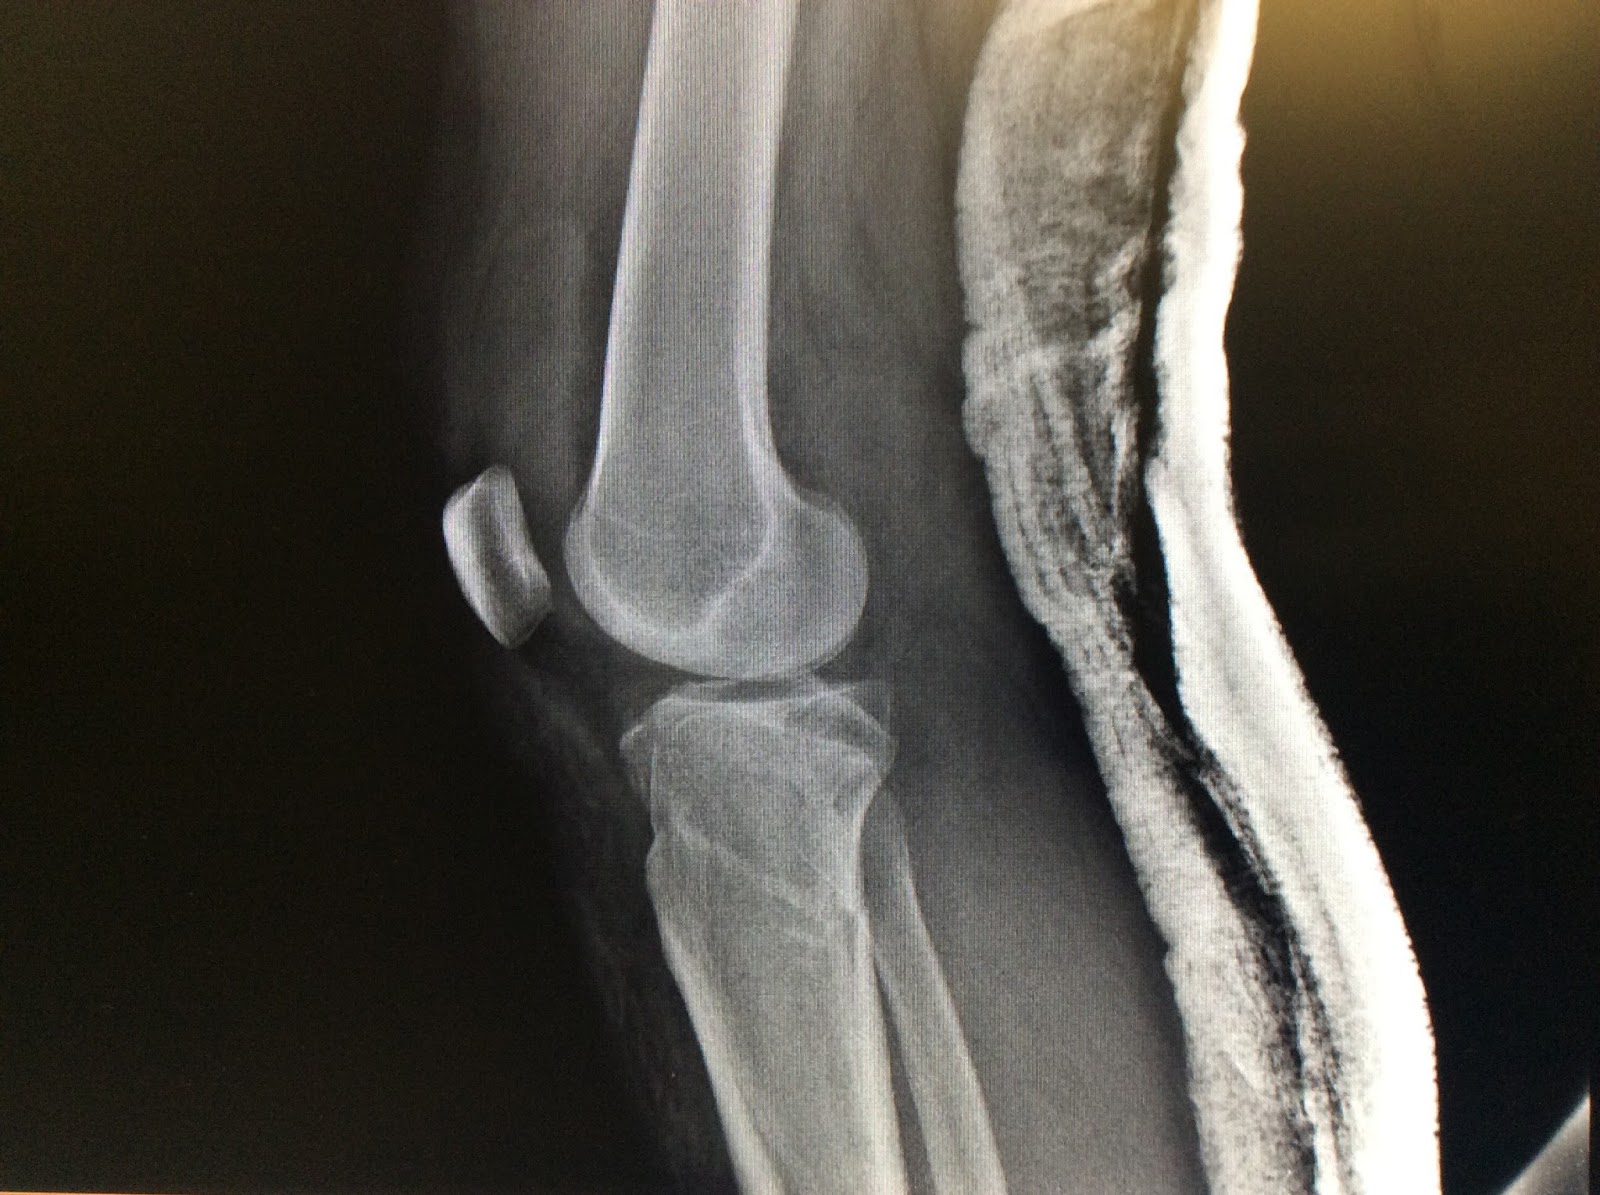

Apoyar Después De Fractura Meseta Tibial, Fractura de la meseta tibial, 3.16 MB, 02:18, 125,672, Clínica CEMTRO, 2014-07-16T11:41:52.000000Z, 3, Tibial plateau fractures – review of current concepts in management, www.orthopaedicsandtraumajournal.co.uk, 1855 x 2006, jpeg, WebPARA LA FRACTURA DE MESETA TIBIAL ACTIVIDAD NO puede apoyar peso. Tiene que usar las muletas para ayudarse a caminar. Puede doblar la rodilla mientras usa la. WebEn todo caso es muy importante no forzar la articulación, el hueso seguramente a los dos meses por ejemplo aún no habrá soldado, Es aconsejable tomar alimentos con vitamina., 20, apoyar-despues-de-fractura-meseta-tibial, Novedades y Muebles WebPARA LA FRACTURA DE MESETA TIBIAL ACTIVIDAD NO puede apoyar peso. Tiene que usar las muletas para ayudarse a caminar. Puede doblar la rodilla mientras usa la. WebEn todo caso es muy importante no forzar la articulación, el hueso seguramente a los dos meses por ejemplo aún no habrá soldado, Es aconsejable tomar alimentos con vitamina.

WebLas fracturas de meseta tibial son lesiones frecuentes cuyo tratamiento óptimo todavía no está definido, existiendo para un mismo tipo de fractura diversas opciones de manejo.

WebUna fractura de meseta tibial Schatzker II con hundimiento de 13 mm... no quedaba otro remedio que operar. Una semana despues del scanner entre en quirofano.. WebSuponiendo un caso de mujer adulta-adulta, con una fractura no desplazada de meseta, en general puede ser tratada conservadoramente, con una descarga de tres semanas y. WebYo se que cuando no se ve una fractura, se puede pedir una tomografía computada que allí sale todo más claro. Yo que vos volvería al traumatólogo sacaría otra placa, según lo.